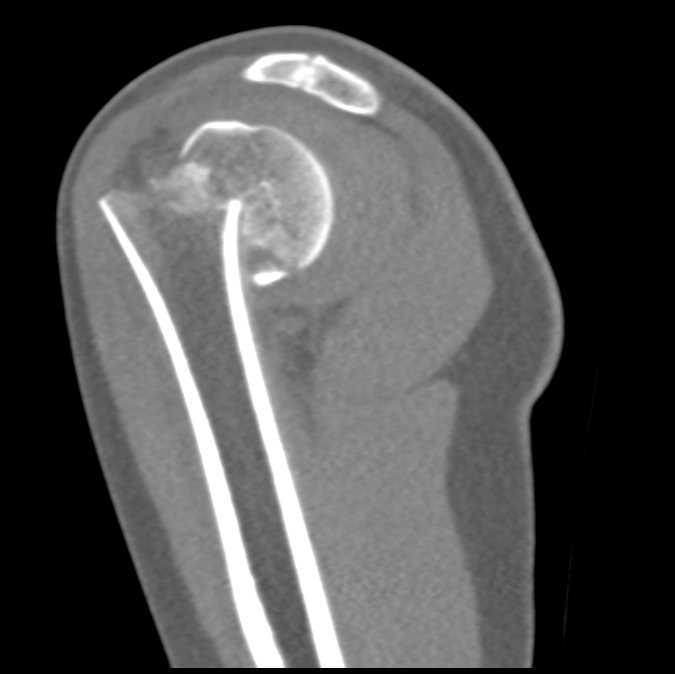

Fracture of the Humerus Neck